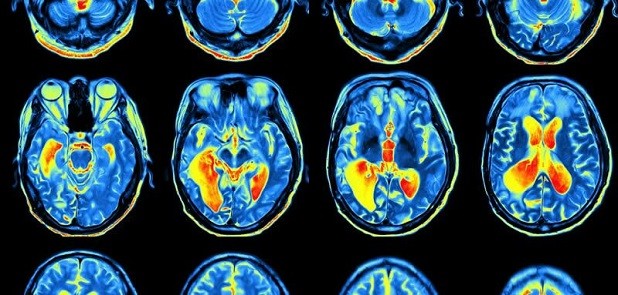

نوروسافاری | محققان از بخش روانشناسی تجربی، مرکز تصویر برداری عصبی یکپارچه وِلکام (WIN) و بخش علوم اعصاب بالینی نوفیلد (وابسته به دانشگاه آکسفورد)، برای رصد تغییرات اتفاق افتاده در مناطق مغزی مرتبط با یادگیری و تجارب آموخته شده از پیمایشگر MRI استفاده کردند در حالی که داوطلبان مشغول تکمیل تکالیفی بودند که پاداشی در پی داشت. همچنین داوطلبان پیش از اسکن، به منظور مقایسه ی تداعی های شخصی شان بین توالی های محرک و پاداش، در دو جلسه ی مقدماتی حضور یافتند.